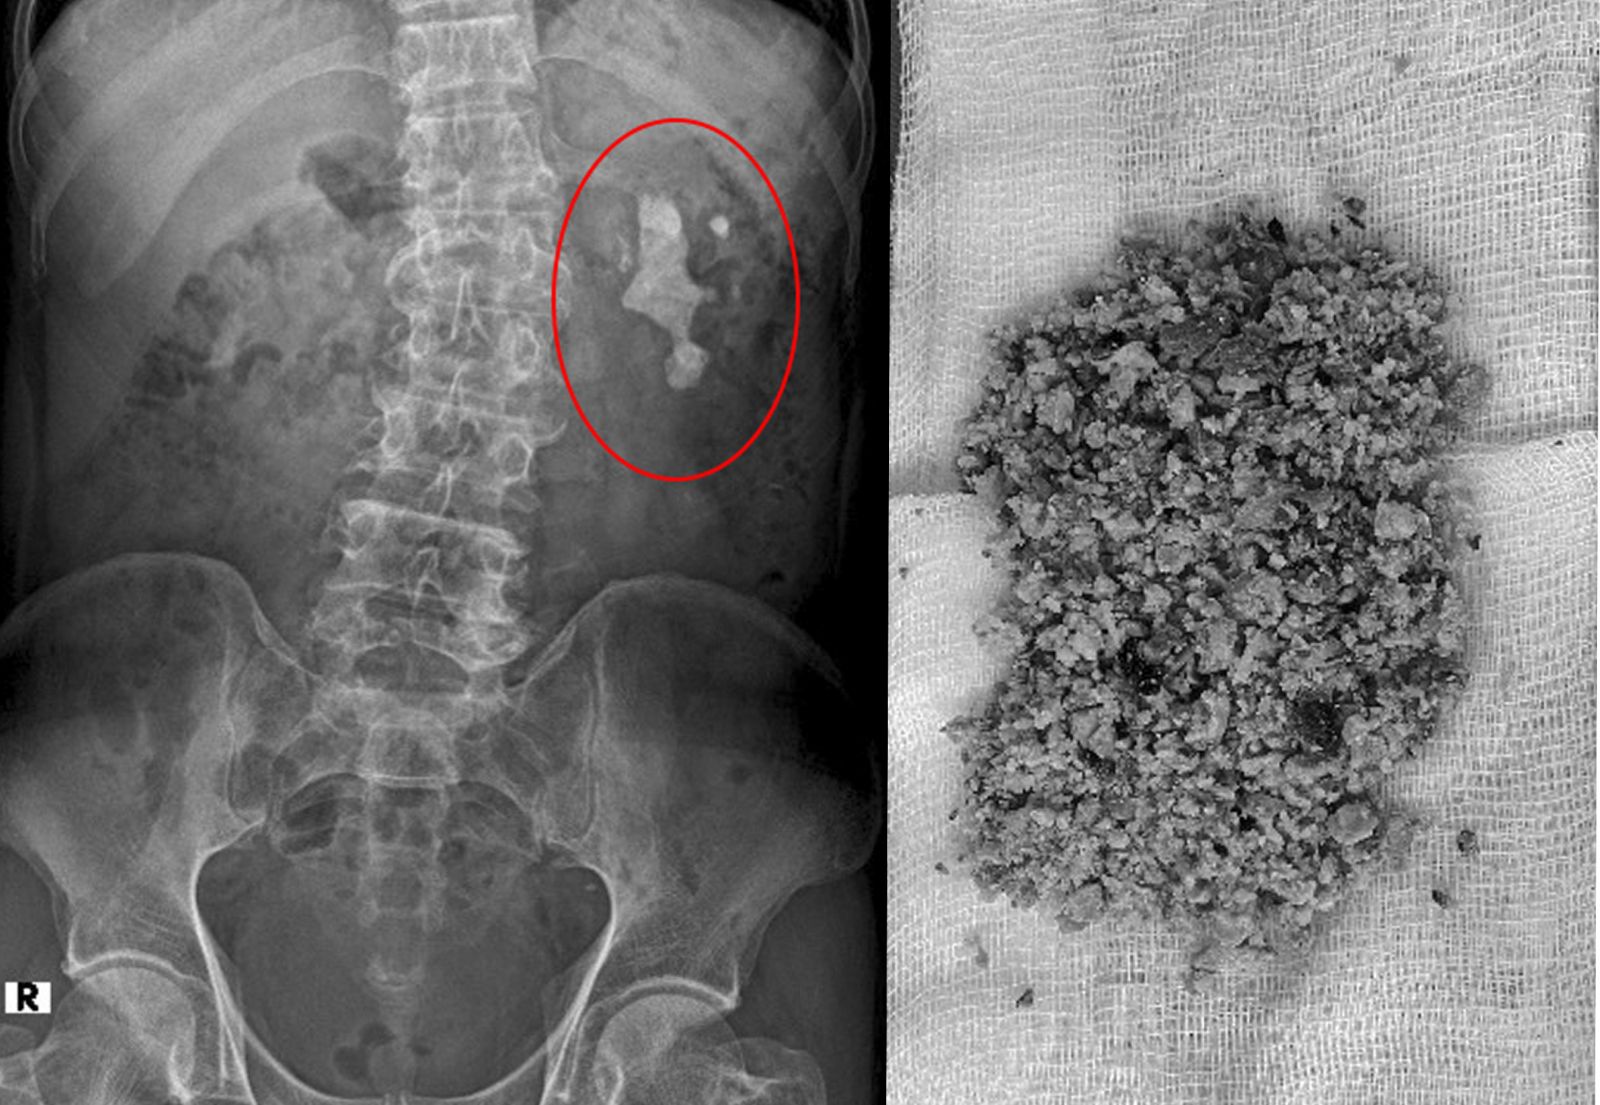

Hình ảnh chụp phim KUB thấy sỏi san hô đài bể thận và sỏi thận sau khi được tán vụn, đưa khỏi cơ thể bệnh nhân.